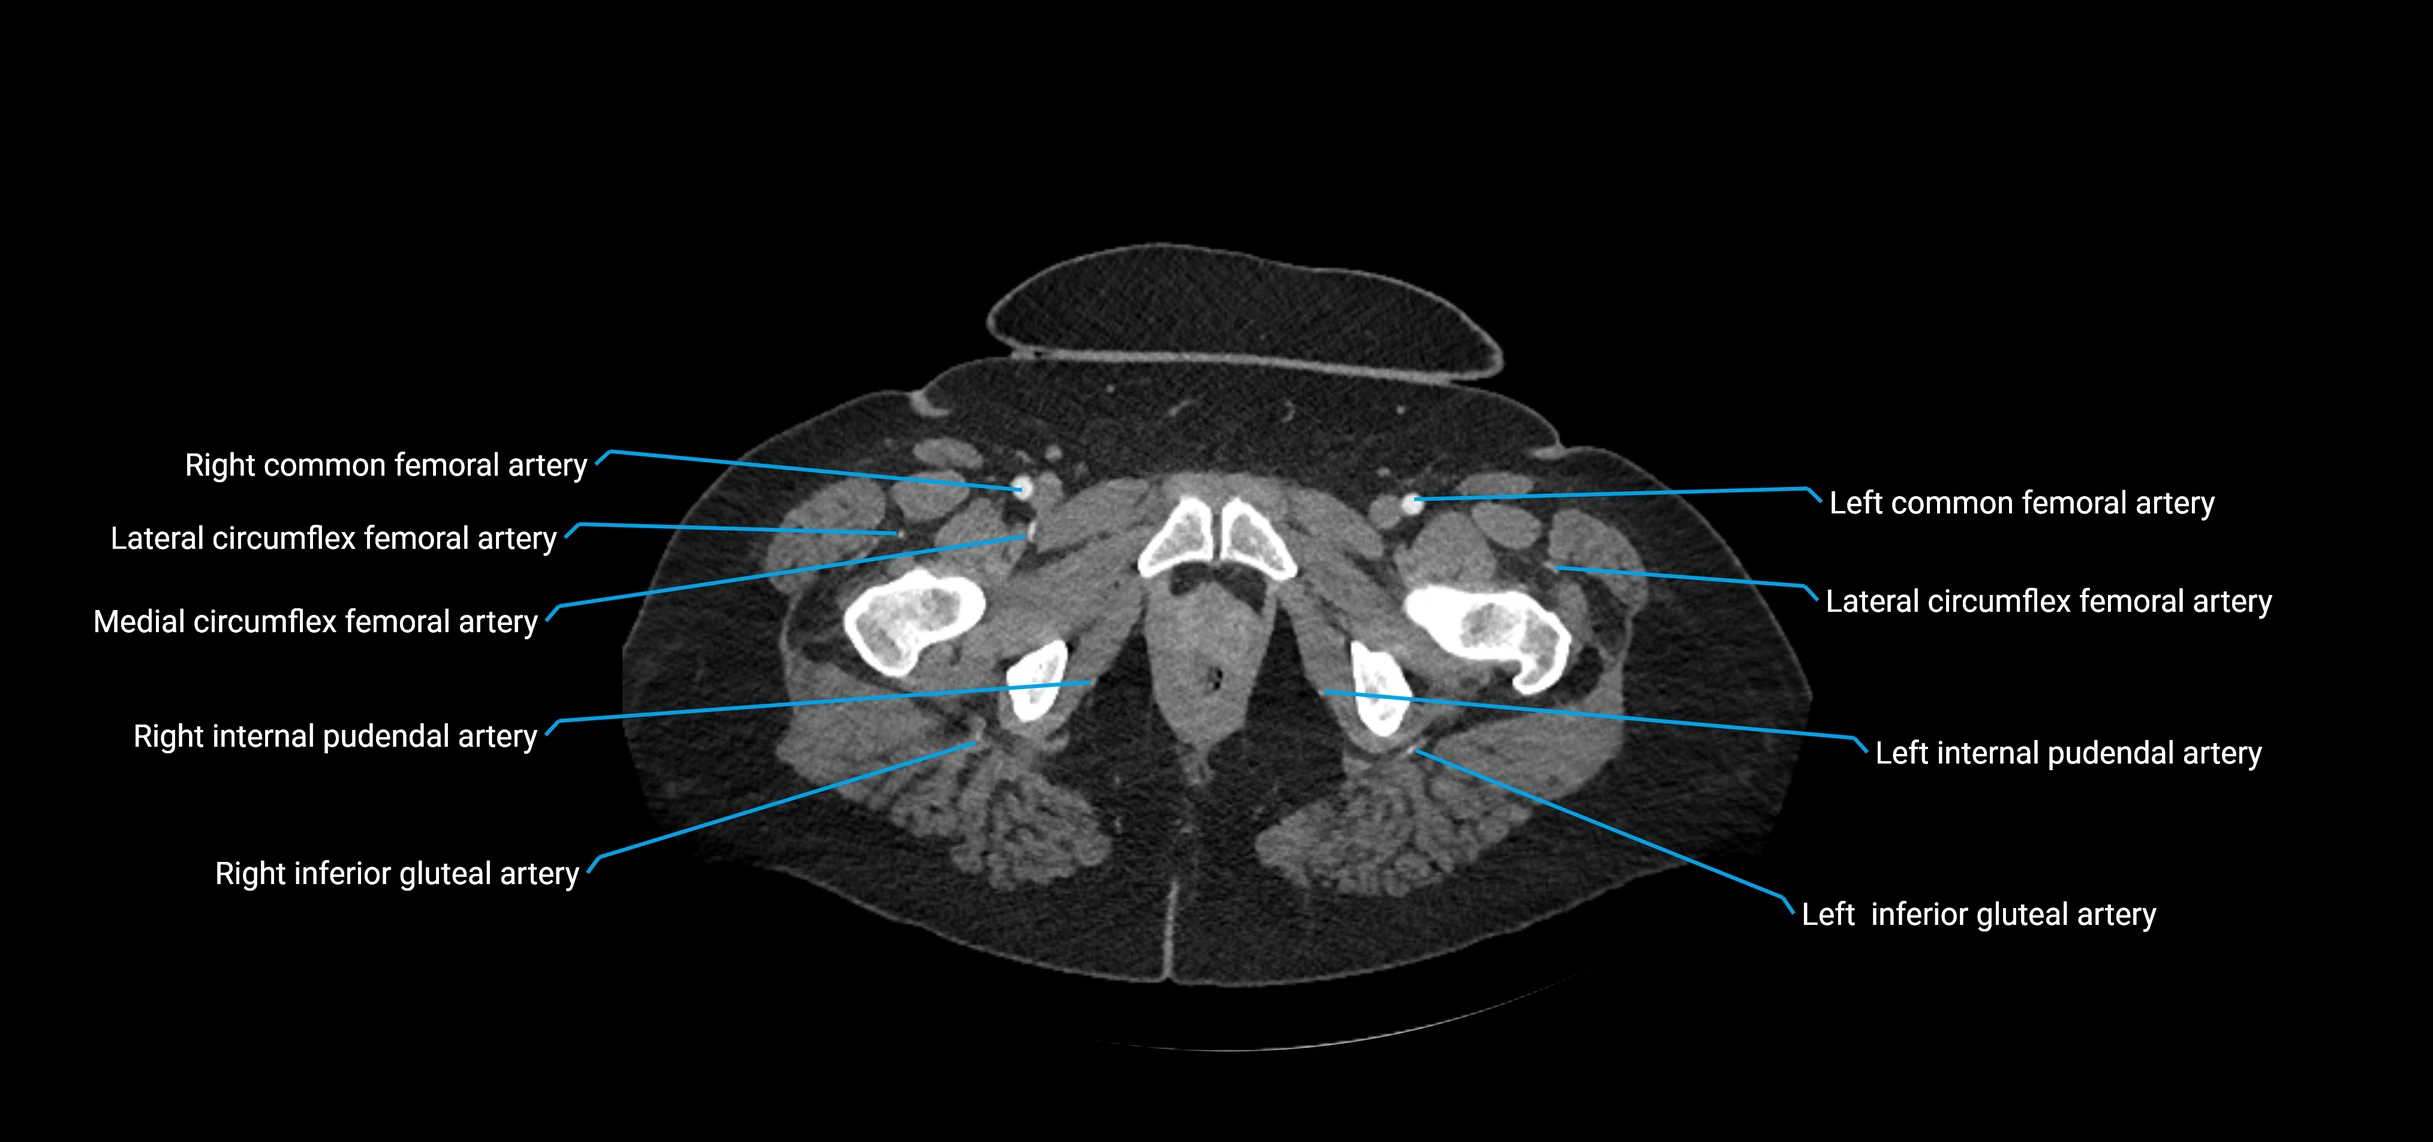

Contrast-enhanced CT (CTA):

• Gold standard for abdominal aortic imaging

• Provides excellent detail of lumen, wall, aneurysm, thrombus, and branch vessels

• Multiplanar and 3D reconstructions help in aneurysm measurement, stent graft planning, and dissection evaluation

• Detects acute rupture, traumatic injury, or occlusion with high sensitivity